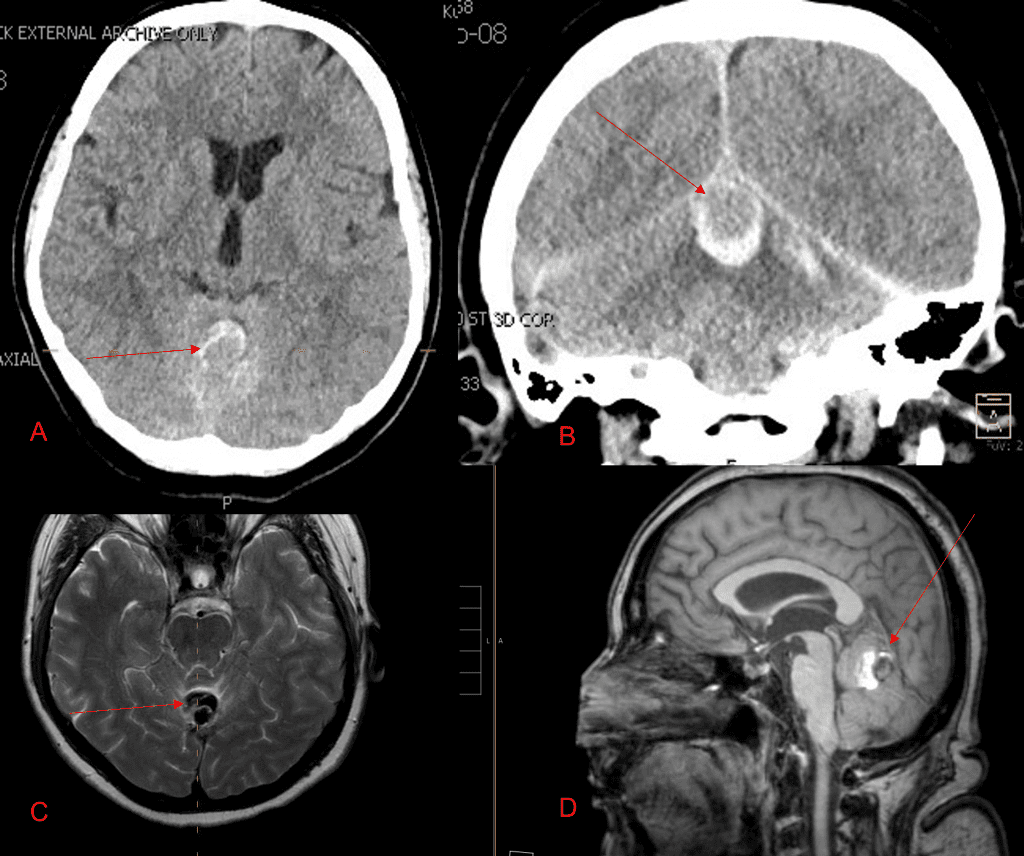

A 55-year-old woman presented with acute onset of severe headache, and possible witnessed seizure. Imaging confirmed intraventricular hemorrhage primarily focused within the fourth ventricle with diffuse subarachnoid hemorrhage within the posterior fossa and along the tentorium as observed on non-contrast CT and MRI of the Brain (Figure 1).

Figure 1. A and B) Non-Contrast CT Axial and Coronal demonstrate large, ruptured Varix/Aneurysm along the Incisura of the posterior fossa which appears to have mixed hemorrhagic components and enhancement on MRI T2 and post contrast imaging (C and D).